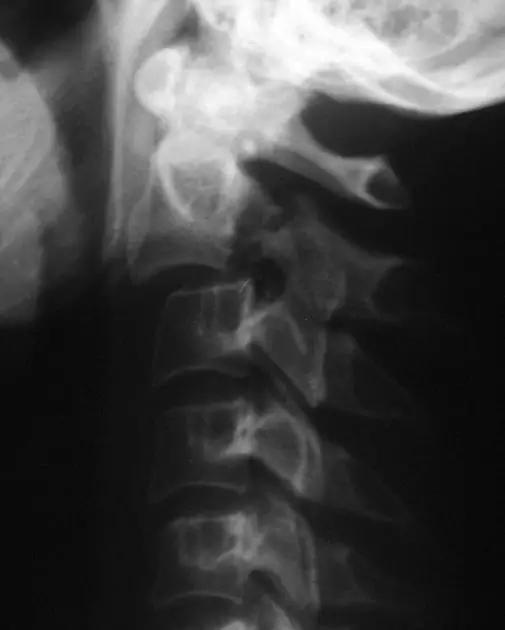

脊柱骨折

1. Burst 骨折

椎体轴向压力造成的骨折,通常发生骨折碎片向外侧的移位。可以发生在颈椎、胸椎或腰椎。

(来源:Radiopaedia)

2. Teardrop 骨折

特指颈椎椎体前下方带有骨折块者,包括屈曲型和伸展型。伸展型损伤指椎体前下缘或下一椎体前上角形成三角形骨块,提示椎体前方稳定结果破坏,治疗不宜伸展位。屈曲型指压缩致使椎体前方三角骨块被挤出如泪滴状,提示前后方稳定结构均遭破坏,常伴脊髓损伤。常需手术治疗。

伸展型 Teardrop 骨折(来源:Radiopaedia)